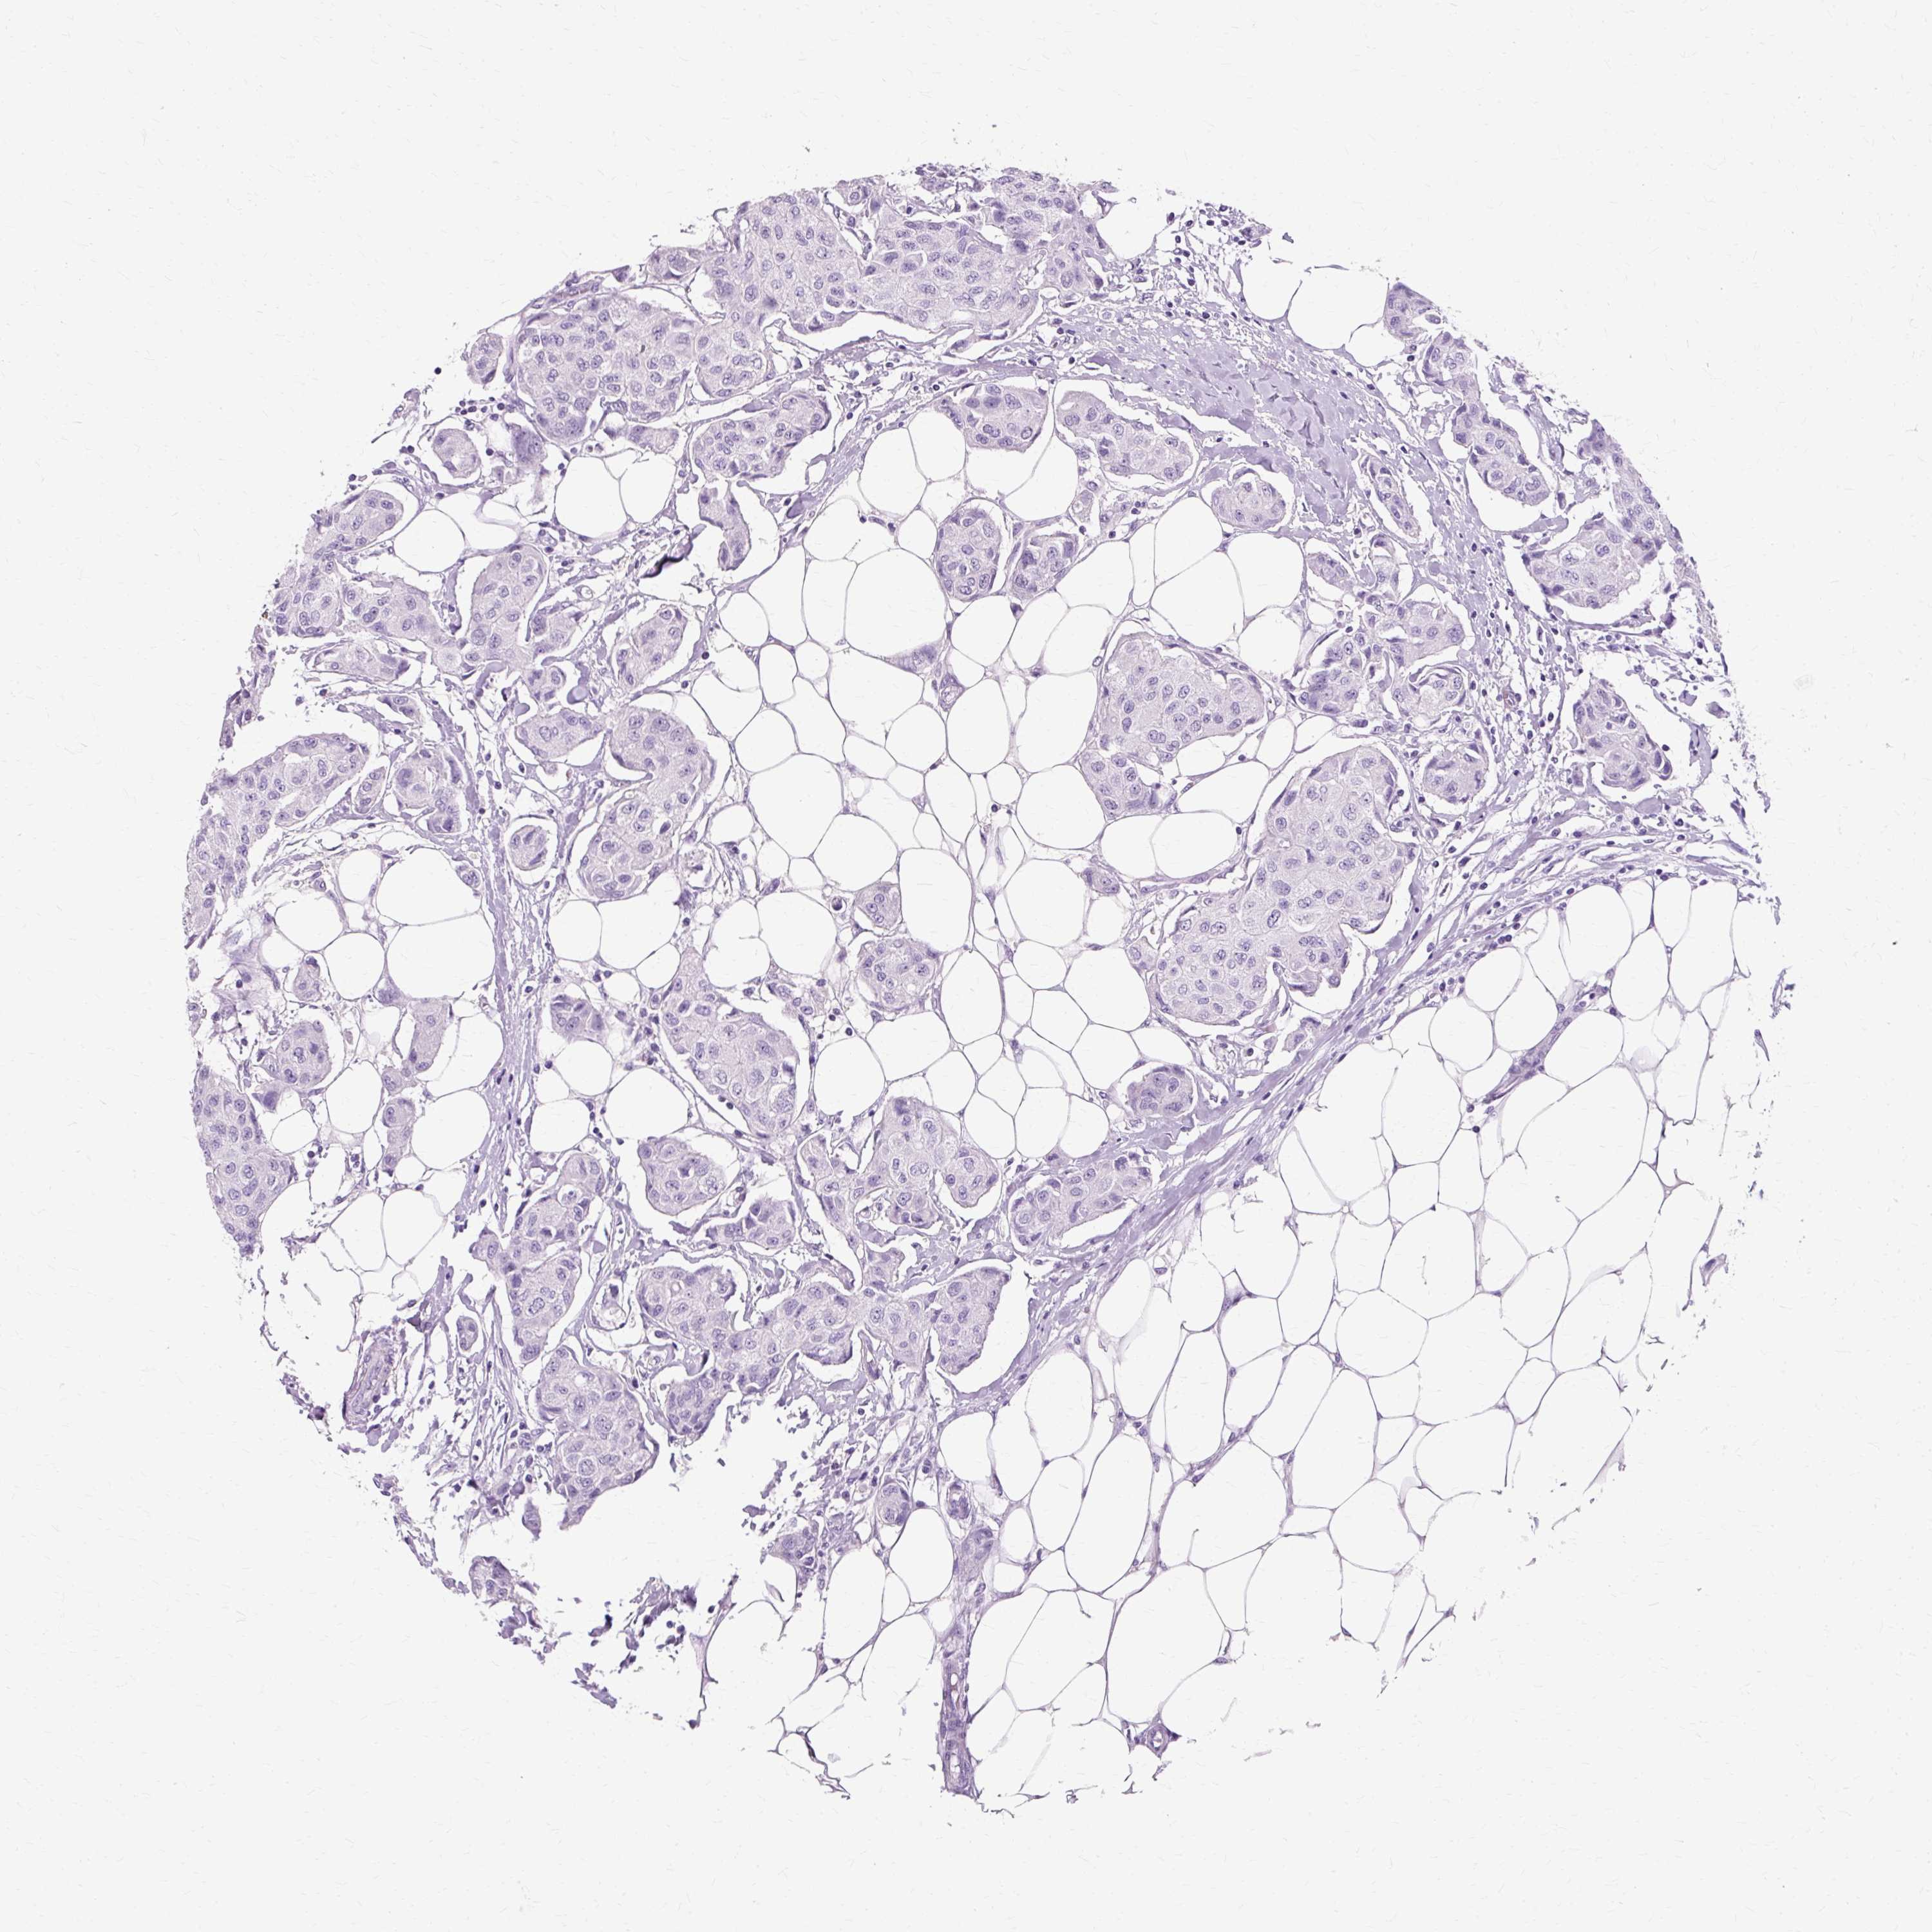

CANCER BREAST CANCER Show tissue menu

Breast cancer

Human cancer